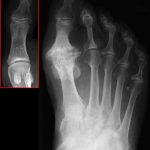

Рентгенография. Является основным методом визуализации для подтверждения диагноза и определения стадии. Снимки выполняются под нагрузкой в прямой, боковой и аксиальной проекциях. Ключевые признаки: сужение суставной щели, остеофиты, субхондральный склероз, кисты. КТ может быть полезна для оценки объема костных разрастаний при планировании хейлэктомии. МРТ применяется редко, в основном для исключения других патологий (остеохондральные дефекты, аваскулярный некроз).

Рентгенологическая классификация

Золотым стандартом является рентгенография стопы в трех проекциях под нагрузкой. Наиболее распространенной в клинической практике является классификация Колина и Шурнаса (Coughlin and Shurnas), модифицированная в 2003 году.